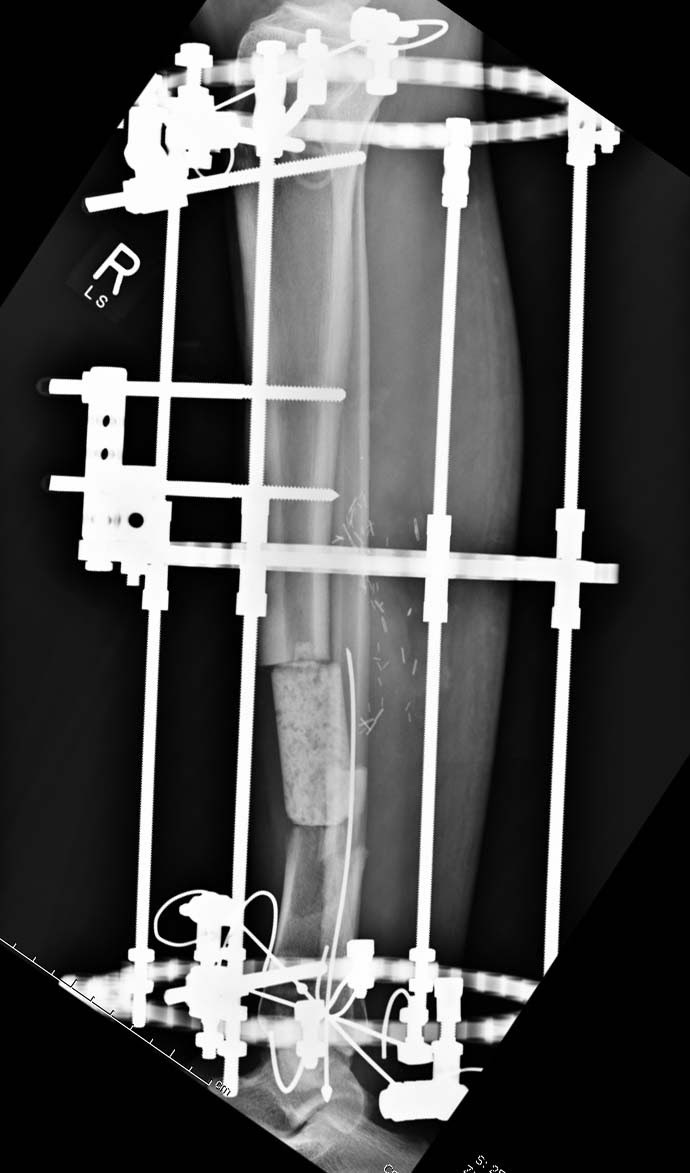

Данный случай не огнестрельная рана, а результат мотоциклетной аварии. Независимо от повреждения при таких обширных дефектах мягких и костной тканей применяется схожая тактика. Как видно, после нескольких I&D для создания “pseudo membrane” применили цилиндрический блок из цемента. Дефект мягких тканей закрыли свободным Anterior Thigh Graft. Из малого доступа цилиндр удален небольшими кусочками, а пространство заполнили бусами для освобождения пространства. По мере приближения регенерата освободили пространство удалением бус через небольшой разрез. Этап созревание регенерата можно было ускорить усилением интрамедуллярным гвоздем, но решили закончить методом Илизарова.

Теперь по поводу данного случая - “спейсер” из цемента предупреждает инфекцию и сохраняет пространство. Но вместо “бус” “цилиндрическая форма” более удобная, вокруг нее образуется ровная трубчатая поверхность “псевдо-мембраны” что в дальнейшей позволит закрыть небольшие дефекты “графтом” или во время удлинения облегчает скольжение регенерата как по трубке.

А воспаление вокруг стержней происходит из-за того, что на бедре мягкие ткани более мобильные, и возле нестабильных стержней образуется реактивное воспаление. Если не лечить, тогда воспаление может перейти в глубокие слои, а в данном случае (fat necrosis), т.е. локальный некроз, который лечится обработкой и созданием стабильности.